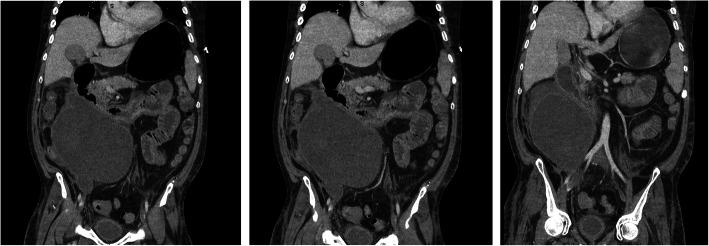

There exists a therapeutic conflict between haemorrhage control and prevention of thromboembolic events following polytrauma and complications are not uncommon. Such opposing therapies can result in unexpected pathophysiology and there is a real risk of misdiagnosis resulting in harm. This case presents a previously unreported complication of prevention and management of thromboembolism- STEMI (ST elevation myocardial infarction) and tamponade mimic secondary to retroperitoneal haematoma.

CASE PRESENTATION

We present a 50-year-old male polytrauma patient who following treatment for presumed pulmonary embolus demonstrated classical clinical findings of myocardial infarction and pericardial tamponade secondary to a retroperitoneal haematoma. This is an event not previously reported in the literature. The risk of adverse outcome by management along the standard lines of STEMI (ST elevation myocardial infarction) was averted through awareness for alternative aetiology via a multi-team approach which resulted in percutaneous drainage of the haematoma and complete resolution of symptoms.